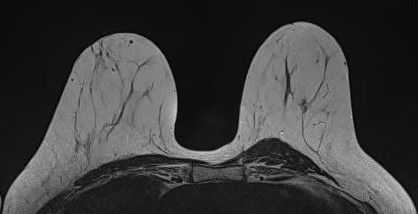

MR-Mammographie

Die Magnetresonanz-Mammographie, kurz MR-Mammographie, ist eine fortschrittliche Bildgebungstechnologie, die in der radiologischen Diagnostik eingesetzt wird, um eine detaillierte und präzise Darstellung des Brustgewebes zu ermöglichen. Dieses Verfahren spielt eine entscheidende Rolle bei der frühzeitigen Erkennung von Brustveränderungen, auch in Fällen, in denen herkömmliche Mammographie oder Ultraschall möglicherweise nicht ausreichend sind. Im Gegensatz zur Röntgenmammographie kommt die MR-Mammographie ohne Röntgenstrahlung aus, was sie zu einer sicheren Option für wiederholte Untersuchungen macht. Für Frauen mit dichtem Brustgewebe, bei denen herkömmliche Mammographien herausfordernder sein können, bietet die MR-Mammographie eine verbesserte Bildqualität und Aussagekraft. Deshalb wird sie von der Europäischen Gesellschaft für Brustbildgebung (EUSOBI) in diesen Fällen sogar im Rahmen der Vorsorge anstatt der konventionellen Mammographie empfohlen.